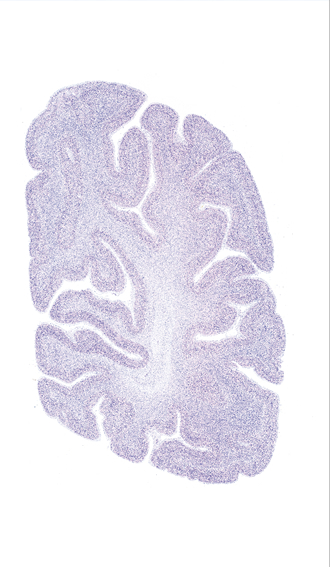

Hi-Resolution Sections · Cells (Nissl Staining) · Virtual Microscopy

Frontal sections (Nissl) from the Atlas Brain:

Slice ID:

r4-1120

Plate NR:

61

Position:

67,1 mm